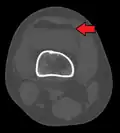

In all injuries to the tibial plateau radiographs (commonly called x-rays) are imperative. Computed tomography scans are not always necessary but are sometimes critical for evaluating degree of fracture and determining a treatment plan that would not be possible with plain radiographs.[10] Magnetic Resonance images are the diagnostic modality of choice when meniscal, ligamentous and soft tissue injuries are suspected.[11][12] CT angiography should be considered if there is alteration of the distal pulses or concern about arterial injury.

3D reconstruction of a CT image of a tibial plateau fracture -